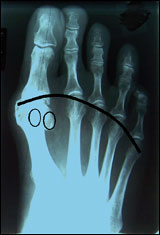

Durch eine einfache Röntgenaufnahme beider Füße

kann das genaue Ausmaß der Abweichung bestimmt werden.

Diese Aufnahme sollte immer im Stehen, also unter Belastung,

durchgeführt werden. |